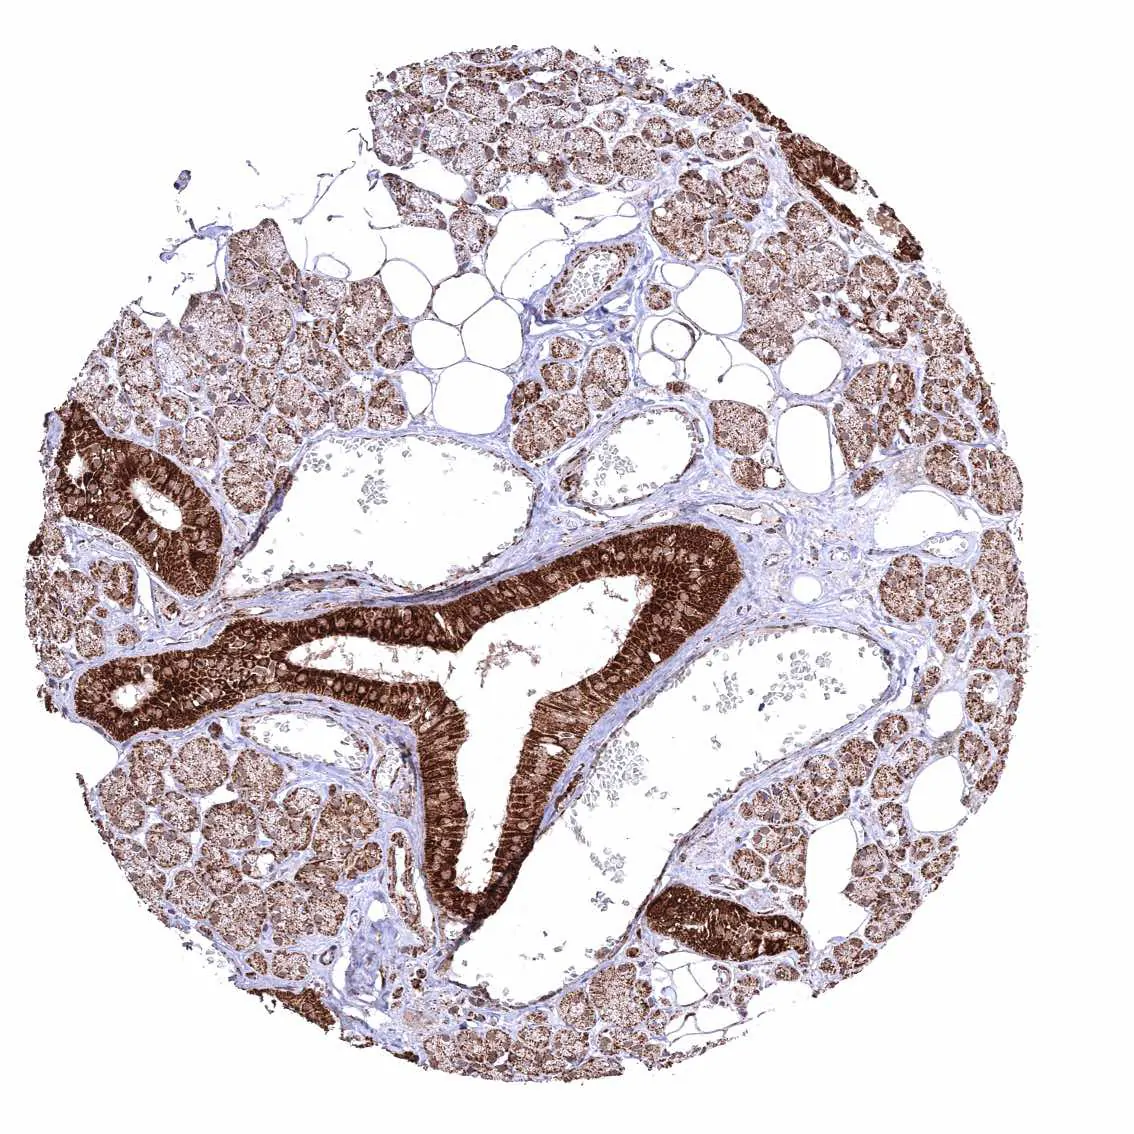

Uterus, endocervix